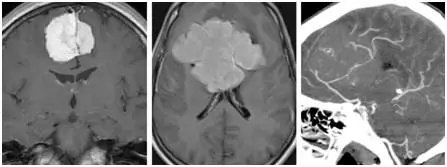

图2.不同体积的镰旁脑膜瘤。CTA显示胼周动脉及胼缘动脉被体积巨大的肿瘤包绕。